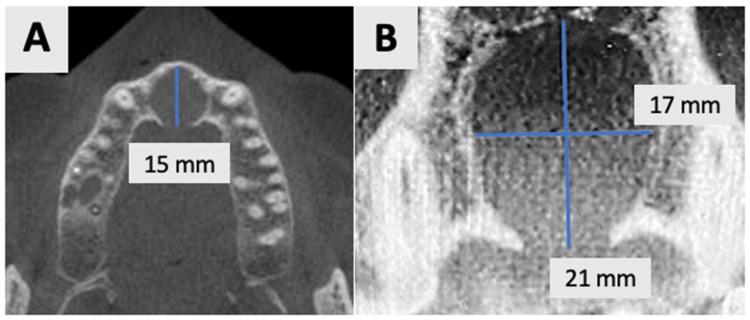

A 35-year-old male patient presented with a large periapical cystic lesion in the maxillary anterior region. Treatment involved marsupialization followed by cyst enucleation and GBR using a resorbable magnesium membrane and bovine xenograft. The magnesium membrane served as a structural support to bridge the bony discontinuity in the palatal bone. Cone-beam computed tomography (CBCT) was used for diagnosis, treatment planning, and follow-up assessments. At 16 months post-treatment, CBCT imaging revealed significant bone regeneration, with restoration of the palatal contour and cortication of the palatal wall. Clinical examination showed asymptomatic teeth with normal mobility and optimal soft tissue healing.

一名35岁男性患者上颌前部出现一个大的根尖囊性病变。治疗包括袋形术,随后进行囊肿摘除术,并使用可吸收镁膜和牛异种移植物进行引导骨再生。镁膜作为一种结构支撑物,用于桥接腭骨的骨不连续处。锥形束计算机断层扫描(CBCT)用于诊断、治疗计划制定和随访评估。治疗后16个月,CBCT成像显示骨再生显著,腭轮廓恢复,腭壁皮质化。临床检查显示牙齿无症状,松动度正常,软组织愈合良好。